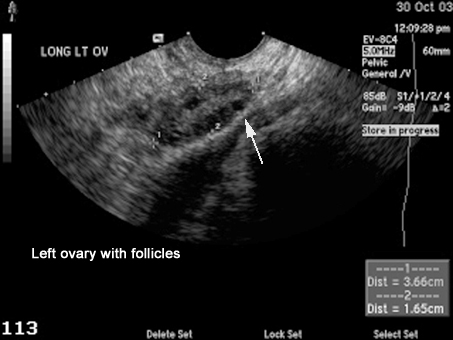

US Pelvis |

|